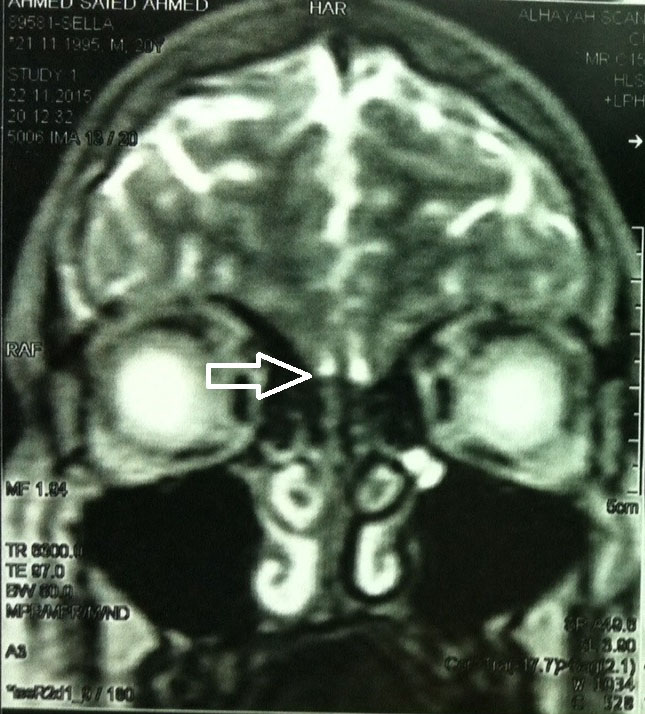

MRI scanning of the brain demonstrated absence of the olfactory bulbs (Figure 1). No other anomalies appeared on the scanning and the semicircular canals were normal. The patient was presumed to have Kal S (6, 7). Neuropsychological assessment was irrelevant and in particular, it did not disclose any mirror movements of the hands or the feet. The patient had also no intellectual disability. Evaluation of hearing inability of the patient was done using tympanometry showing sensorineural hearing impairment. An advice for a cochlear transplantation was given.

Figure 1. MRI scan of the brain identifying deficiency of the olfactory bulbs; the arrow denotes the presumed location of the olfactory bulbs.